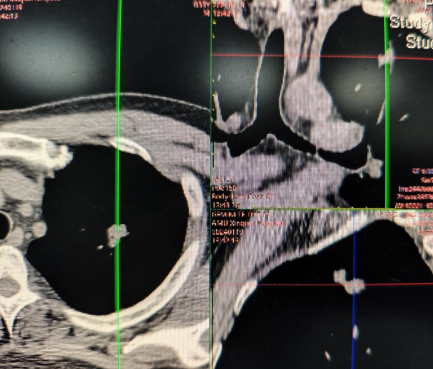

通过智能影像筛查、实体/液体活检技术、内镜精查活检、遗传风险评估、动态监测等多种先进技术发现癌前病变或早期肿瘤,实现早诊早治、防治结合。